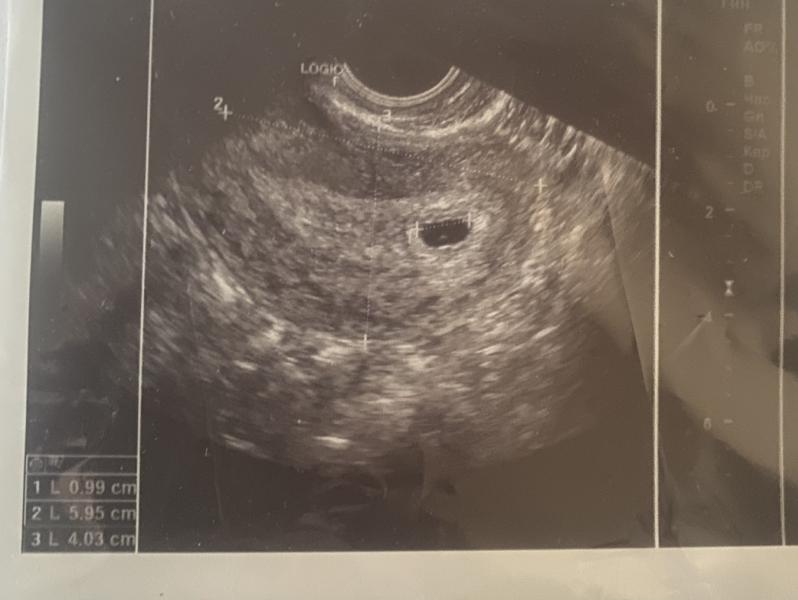

Первое фото нашей радости!